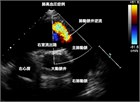

1. 心エコー検査(推奨度1)。